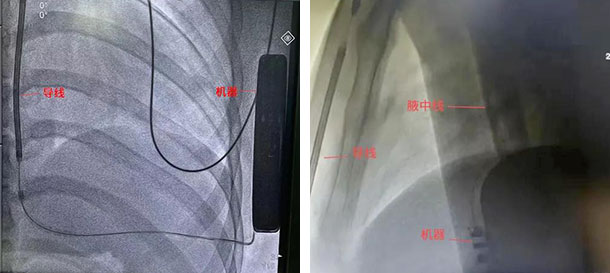

连接脉冲发生器与电极,置入囊袋并固定,排出空气后关闭深筋膜层,逐层缝合手术切口,随后进行除颤阈值测试,给予50Hz,200mA交流电诱发室颤,S-ICD准确识别,65J能量一次除颤成功,除颤阻抗59Ω。术区覆盖无菌纱布,弹力绷带加压包扎。手术耗时约1小时。

术中DFT测试

术后影像